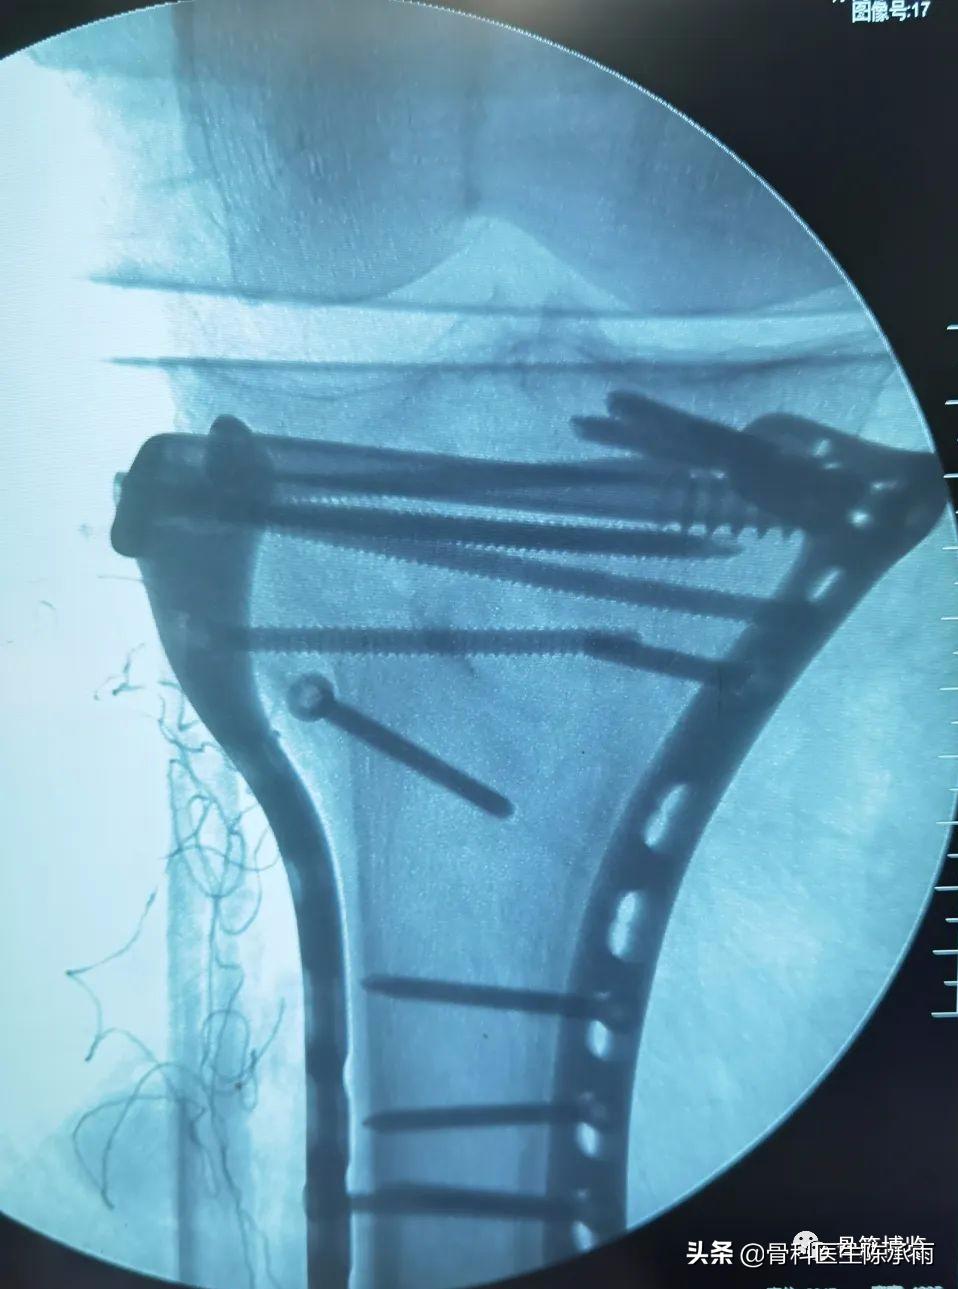

这2例患者皮肤条件差,全身多发骨折,小腿皮肤条件差,1例筋膜高压切开,1例整个小腿布满张力性水泡,胫骨骨折都在伤后30天才能手术。

下例胫平台骨折皮肤条件差,内侧板取两端小切口置入内板固定。胫骨结节处撕脱骨折以1枚拉力螺钉固定。